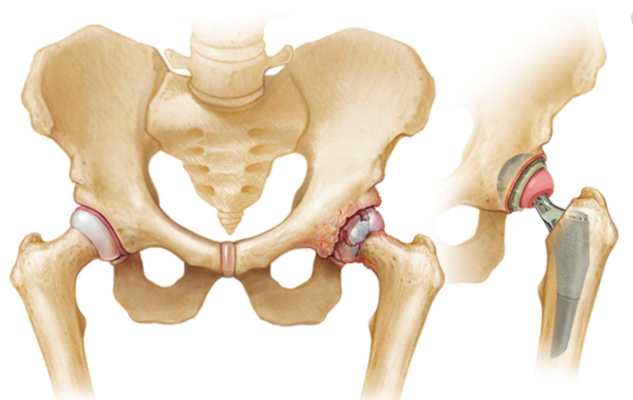

- Đau khớp háng nặng khi vận động và chịu trọng lượng và giới hạn vận động rõ do tổn thương khớp và mất sụn khớp do thoái hóa, viêm khớp do chấn thương hoặc dạng thấp, viêm cột sống dính khớp, hoại tử xương (vô mạch) dẫn đến suy giảm chức năng và chất lượng cuộc sống.

Trước đây, THA chủ yếu dành cho những bệnh nhân lớn hơn 60 -65 tuổi hoặc những người trẻ tuổi rất ít hoạt động bị tổn thương nhiều khớp bởi vì thời gian dự kiến hoạt động của khớp nhân tạo < 20 năm. Với các bệnh nhân trẻ tuổi bị tổn thương khớp nặng, phẫu thuật thay bề mặt khớp (bảo tồn hơn THA), là một loại phẫu thuật thay thế có thể được xem xét. Tuy nhiên, nhờ sự tiến bộ trong thiết kế, vật liệu, và đặc biệt là cố định không cần xi măng do đó mở rộng tiêu chuẩn chọn lựa bệnh nhân, THA cũng được xem xét ở những bệnh nhân trẻ hơn, những người hoạt động mức trung bình. Với những người này phẫu thuật viên cần tư vấn về khả năng phải phẫu thuật chỉnh hình khớp lại về sau.

Thiết kế khớp giả và vật liệu

Hiện nay thường gồm phần đùi bằng kim loại bất hoạt (cobalt-chrome và titanium) và phần ổ cối bằng polyethylene đậm độ cao. Một số thiết kế khác như hệ thống kim loại/kim loại và các hệ thống sử dụng bề mặt bằng gốm sứ.

Cố định có xi măng và không xi măng

Các phẫu thuật THA đầu tiên sử dụng xi măng acrylic, chất methylmethacrylate, để cố định khớp nhân tạo. Cố định xe măng cho phép chịu trọng lượng sau phẫu thuật rất sớm và rút ngắn thời gian PHCN, trong khi trước khi sử dụng cố định bằng xi mặng bệnh nhân phải hạn chế chịu trọng lượng và vận động hàng tháng trời. Cố định bằng xi măng vẫn còn được sử dụng cho đến nay nhưng cũng có những nhược điểm. Một biến chứng sau phẫu thuật vài năm là lỏng các thành phần khớp giả vô khuẩn ở giao tiếp xương-xi măng. Sự lỏng lẻo này dẫn đến đau háng tái phát và cần phải phẫu thuật lại. Những người trẻ tuổi, hoạt động thường bị lỏng găn khớp hơn là những người già ít hoạt động.

Vấn đề lỏng cơ học của các mảnh ghép có xi măng, thường là thành phần ổ cối, đã tạo nên sự xuất hiện và sử dụng cố định không xi măng (sinh học). Cố định không xi măng có thể bằng cách sử dụng các khớp nhân tạo bề mặt lỗ rỗ cho phép xương có thể phát triển vào bên trong bề mặt như bánh mỳ hay sử dụng kỹ thuật ép vừa khít không xi măng. Các thành phần đùi trơn (không lổ rổ) cũng được xử dụng trong tạo hình khớp không xi măng. Một số thành phần được sản xuất với một lớp lót là hợp chất có hoạt tính sinh học được gọi là hydroxyapatite để kích thích sự phát triển xương ban đầu. Mô xương phát triển vào trong xảy ra trong thời gian 3-6 tháng với sự tái cấu trúc xương tiếp tục ngoài thời gian đó.

Các cải tiến của cố định xi măng và không xi măng đã tiếp tục, cũng như các tranh cãi về ưu điểm, chỉ định và bất lợi của hai dạng cố định này. Cố định xi măng thường được sử dụng cho các bệnh nhân bị loãng xương, dự trữ xương kém, người già trong khi cố định không xi măng thường là chọn lựa của các bệnh nhân dưới 60 tuổi, hoạt động và có chất lượng xương tốt.

Bởi vì tỉ lệ lỏng của mảnh ghép đùi xi măng thấp, mảnh ghép ổ cối xi măng cao, hiện nay người ta có thể chọn lựa giải pháp lai với thành phần ổ cối không xi măng và thành phần đùi xi măng. Trong một vài tuần đầu sau mổ, phương pháp cố định có thể ảnh hưởng sự chịu trọng lượng của bệnh nhân khi di chuyển và hoạt động chức năng.